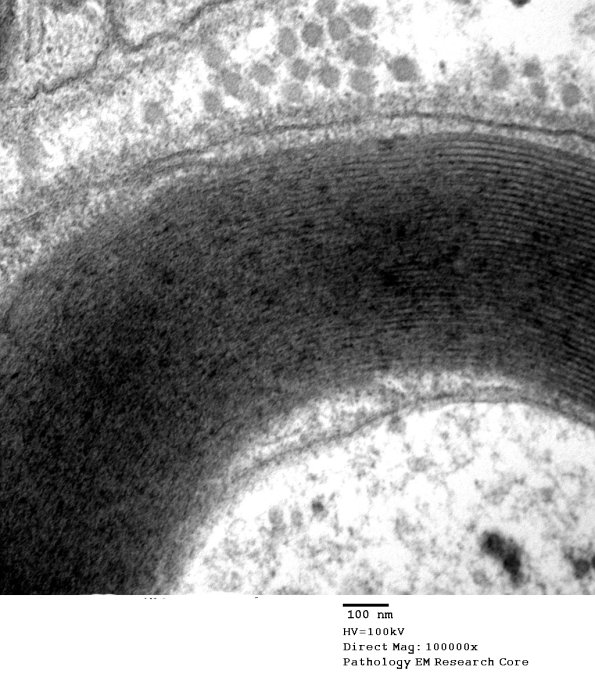

Internal mesaxon of a small myelinated axon with normal substructure. (Electron micrograph)